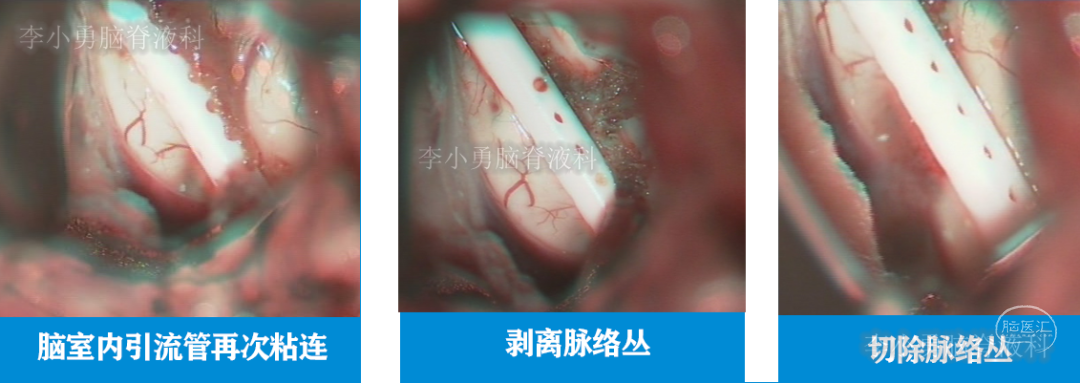

当天进行了开颅手术,术中发现脑室内引流管再次被脉络丛粘连,并切除脉络丛(图-21)。

图-21:术中过程